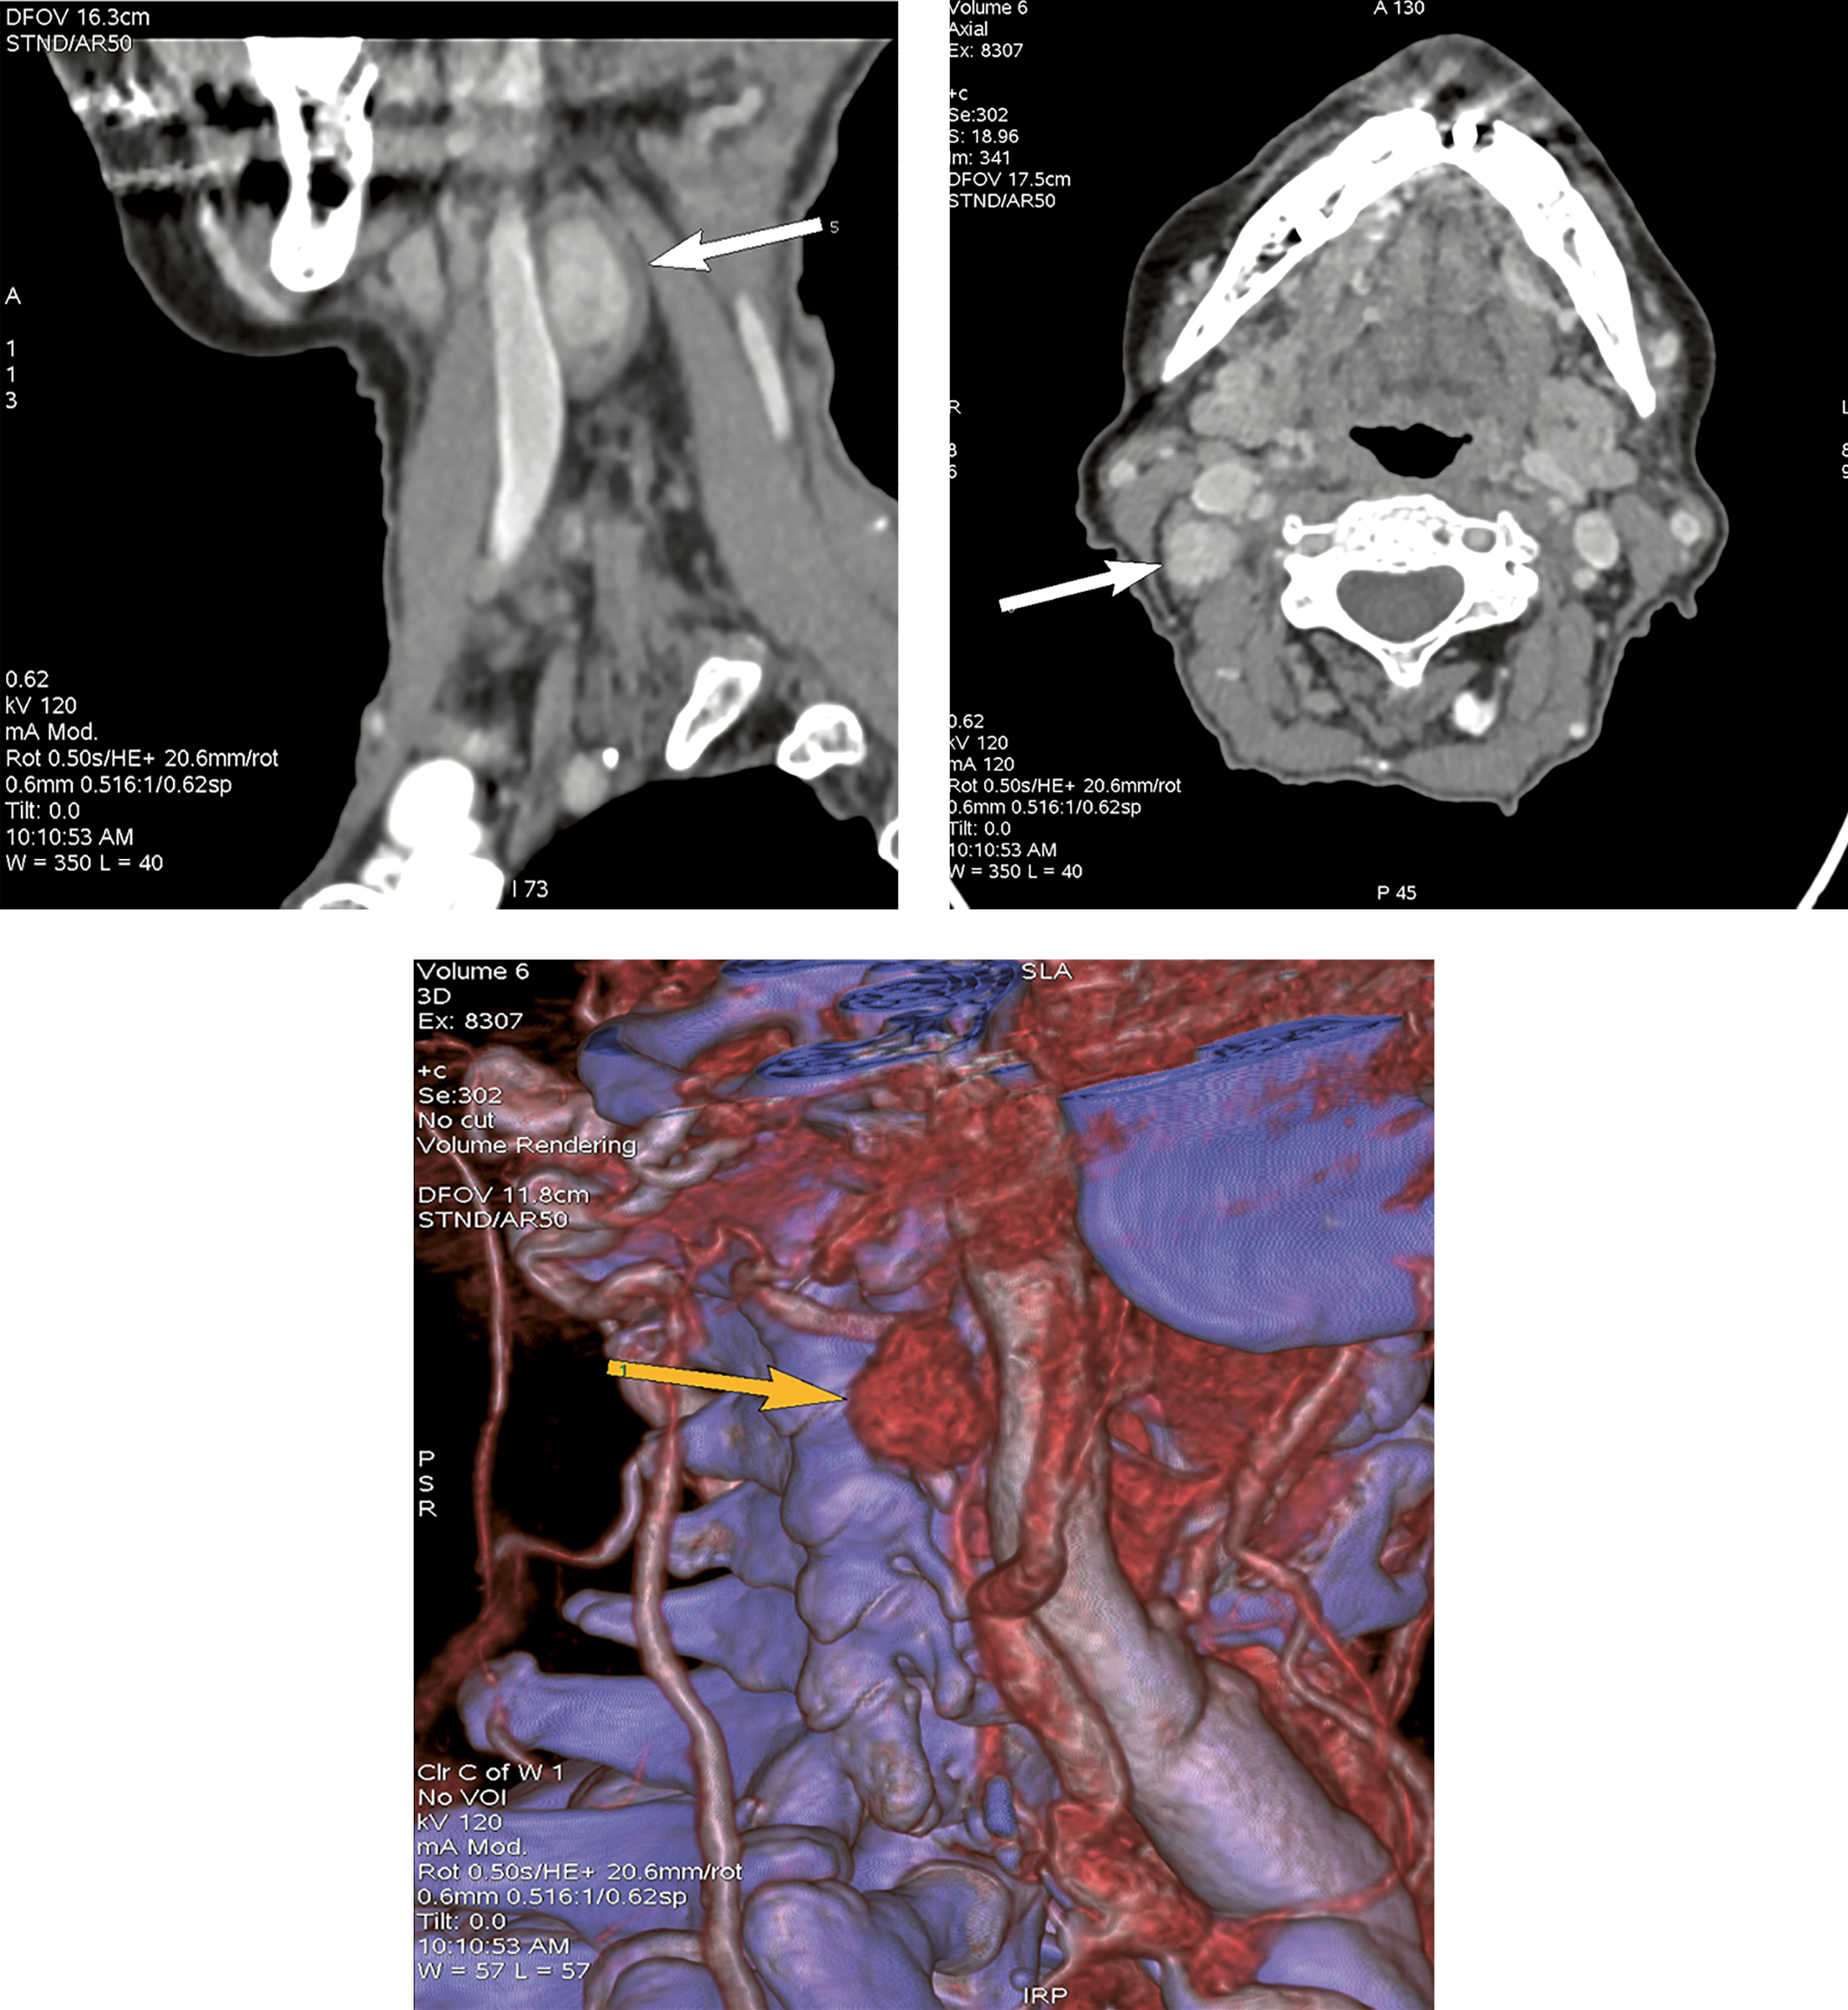

В декабре 2021 г. были проведены сцинтиграфия ОЩЖ с 99mTc-технетрилом и однофотонная эмиссионная КТ, совмещенная с рентгеновской КТ (ОФЭКТ/КТ) в ГНЦ РФ ФГБУ «НМИЦ эндокринологии» Минздрава России (далее — НМИЦ эндокринологии), а также мультиспиральная КТ шеи с контрастным усилением. Именно при помощи ОФЭКТ/КТ впервые было выявлено атипично высоко расположенное образование с признаками интенсивного накопления радиофармпрепарата размерами 18х11х33 мм справа, позади правой внутренней яремной вены, медиальнее m. sternocleidomastoideus на уровне правой поднижнечелюстной слюнной железы (рис. 1).

Рисунок 1. ОФЭКТ/КТ с 99mTc-технетрилом от декабря 2021 г.

Красными метками отмечено образование ОЩЖ.

В представленном нами клиническом случае планарная сцинтиграфия не позволила локализовать аденому ОЩЖ, поскольку аденома располагалась рядом с поднижнечелюстной слюнной железой и при данном методе исследования не дифференцировалась на фоне физиологического накопления 99mTc-технетрила в слюнной железе. И только объемное изображение ОФЭКТ/КТ позволило обнаружить аденому ОЩЖ. В данном клиническом случае пожилой возраст пациентки, эктопическое расположение образования, расположение опухоли ОЩЖ вблизи возвратного гортанного нерва, потенциально осложняющее хирургическую тактику, а также наличие тяжелой сопутствующей кардиоваскулярной патологии значимо повышали операционные риски. В силу отсутствия топических данных на протяжении длительного времени своевременное радикальное хирургическое лечение не представлялось возможным. Вышеуказанные факторы, а также возможность поддержания нормокальциемии на фоне медикаментозной терапии послужили причиной выбора консервативной тактики лечения пациентки.